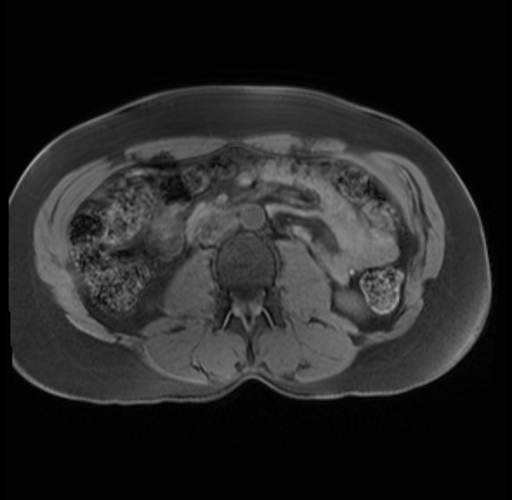

Imaging Analysis

Look through the patient's CT scan to identify any areas of concern for the necessary procedure.

Based on your CT findings, which issue(s) are present and would give reason for "planned slowing down moment(s)" in this case?